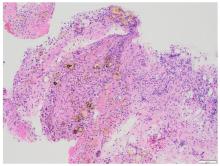

Zhongwei ZHOU,Wei DU,Yu NING,Jing YU,Fengyou GUO,Xueliang YANG.

SMARCB1/INI1-deficient undifferentiated pancreatic carcinoma: A case report and literature review

[J]. Journal of Jilin University(Medicine Edition), 2026, 52(2): 523-529.